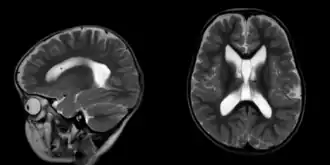

Seizure disorders are common,[3] and may include generalized tonic–clonic, absence, rolandic and febrile seizures.[4] Neuroimaging usually reveals benign brain anomalies.[5] Other neurodevelopmental findings include mildly decreased muscle tone, poor motor coordination and unusual walking. Feeding difficulties—made worse by decreased tone of muscles—begin in infancy and may lead to failure to thrive.[6] Children can also experience reflux and constipation.[7] Heart defects such as ventricular septal defect and lung conditions like tracheomalacia occur rarely.[1]

Growth parameters and milestones are regularly evaluated to monitor progress. Early intervention is often necessary, and involves physical therapy to improve motor skills, occupational therapy to enhance daily functioning and speech therapy to support language development. An Individualized Education Program can be used to tailor education to a child's cognitive profile and address specific learning needs. Individuals who have experienced seizures may undergo further evaluation with electroencephalography and MR brain.[1] Anticonvulsant medications may be needed based on clinical history.[2] In some cases, temporary feeding tube placement has been required due to failure to thrive and persistent feeding difficulties.[11]